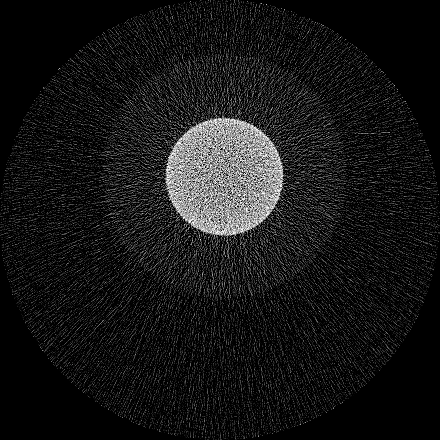

Figure 3 shows a single slice spectral reconstruction of the Ti phantom. The cupping effect is prominent in the low energy range and decreases in the high energy acquisitions. The thresholds were determined to provide a trade-off between reduced photon noise and cupping effect. The spectral images for the energy ranges 55 to 80 keV and 62 to 80 keV exhibit reduced cupping effect while the 15 to 80 keV reconstruction has low quantum noise and shows good contrast in non-metal regions. In figure 4, a horizontal line profile passing through the origin of the metal cylinder shows cupping effect in the different energy ranges. Without the use of any hardware filters, a significant reduction in the cupping effect is noticeable in figure 4c. The reconstruction corresponding to the energy range from 62 to 80 keV suffers from severe photon limitation giving rise to statistical noise. Any significant increase in tube current and/or exposure time for this scan resulted in detector saturation in non-metal regions.